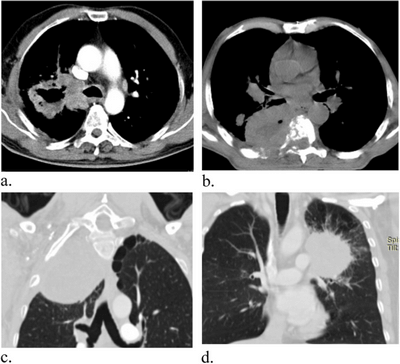

КТ часто використовується для виявлення раку на ранніх стадіях або для підтвердження підозри на діагноз. КТ може виявити наявність пухлин, їх розмір і розташування, а також те, чи поширилися вони на інші частини тіла. КТ особливо корисна для виявлення солідних пухлин, таких як рак легенів, печінки та підшлункової залози.

КТ надає зображення з високою роздільною здатністю, що дозволяє детально візуалізувати внутрішні структури організму. Це полегшує виявлення та локалізацію пухлин та інших патологій.